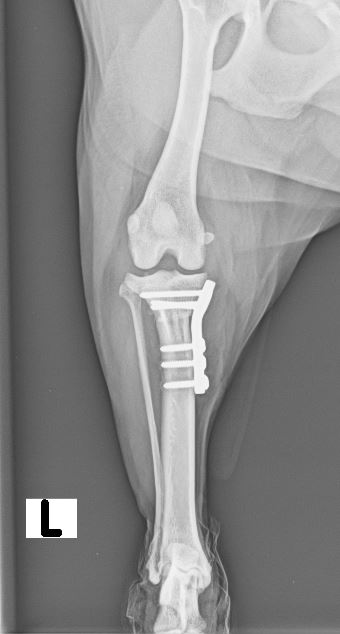

Umfangsvermehrungen an unterschiedlichen Stellen im Körper können in jedem Alter des Hundes entstehen und müssen in vielen Fällen chirurgisch entfernt werden. Um anschließend eine genaue Diagnose und zukünftige Prognose stellen zu können, wird das entnommene Gewebe in der Regel in ein externes Labor gesendet und liefert bereits einige Tage später ein Ergebnis. Unser erfahrenes Operationsteam und die perfekt auf den jeweiligen Hund abgestimmte Narkose sind ein entscheidender Bestandteil für die erfolgreiche Operation Ihres Lieblings.